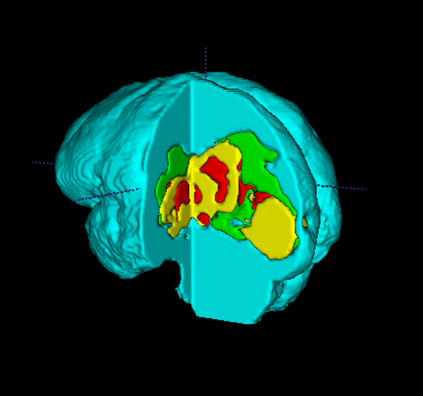

Segmentation of brain tumor from magnetic resonance imaging (MRI) is a vital process to improve diagnosis, treatment planning and to study the difference between subjects with tumor and healthy subjects. In this paper, we exploit a convolutional neural network (CNN) with hypercolumn technique to segment tumor from healthy brain tissue. Hypercolumn is the concatenation of a set of vectors which form by extracting convolutional features from multiple layers. Proposed model integrates batch normalization (BN) approach with hypercolumn. BN layers help to alleviate the internal covariate shift during stochastic gradient descent (SGD) training by zero-mean and unit variance of each mini-batch. Survival Prediction is done by first extracting features(Geometric, Fractal, and Histogram) from the segmented brain tumor data. Then, the number of days of overall survival is predicted by implementing regression on the extracted features using an artificial neural network (ANN). Our model achieves a mean dice score of 89.78%, 82.53% and 76.54% for the whole tumor, tumor core and enhancing tumor respectively in segmentation task and 67.90% in overall survival prediction task with the validation set of BraTS 2018 challenge. It obtains a mean dice accuracy of 87.315%, 77.04% and 70.22% for the whole tumor, tumor core and enhancing tumor respectively in the segmentation task and a 46.80% in overall survival prediction task in the BraTS 2018 test data set.